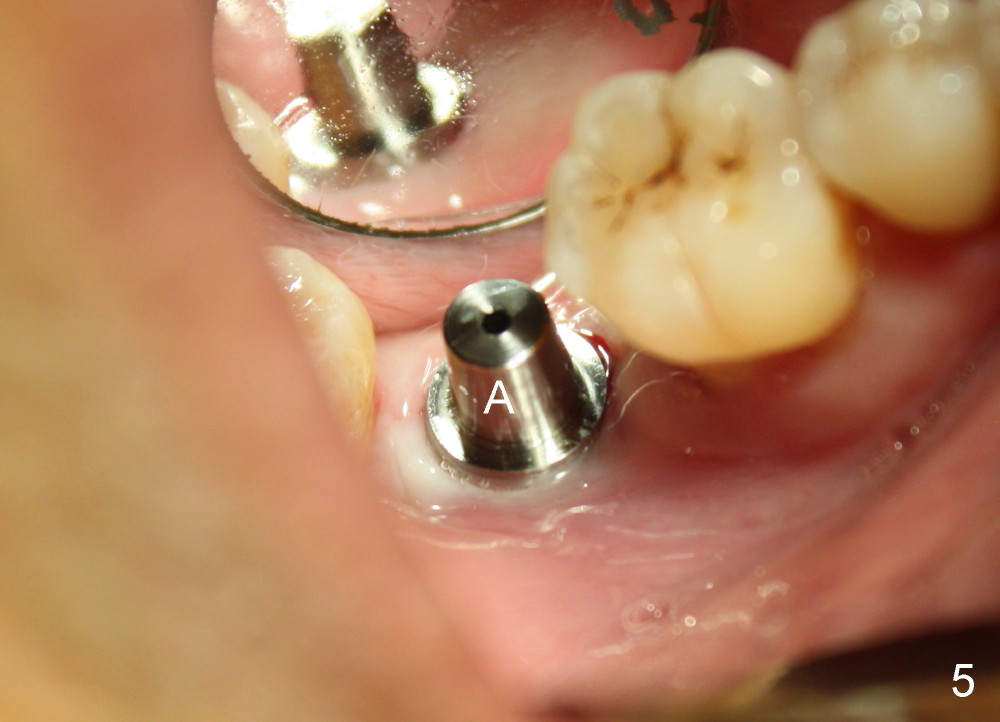

Luckily the patient returns for #31 implantation 4 months post socket preservation. Bone forms in the alveolus and above (Fig.1 black and white arrowheads, respectively). A 6 mm tissue punch is used to open the wound (Fig.2). Osteotomy forms using bone expanders, reamers and taps (Fig.3: 6x14 mm tap). Without infection, local anesthesia is more easily achieved than immediate implant when infection exists. The depth is controlled more readily with delayed implantation. Following adjustment of trajectory, a 7x11 mm implant is placed with insertion torque 60 Ncm (Fig.4 I). Fig.5 shows that the implant obliterates the wound; an abutment (A) is placed to retain perio dressing. With formation of new bone from socket preservation, insertion torque seems to be more easily obtained with the short implant. There is no space to re-use the harvested bone (Fig.6). The implant remains stable postop. Apparent new bone is forming toward the distal coronal threads 5 months postop (Fig.7). The bone around the implant remains stable 17 months post cementation (Fig.8), although there is an episode infection at the neighboring tooth (#30). The patient is more eager to have implants for the maxilla, since the flipper has lost. After implant placement at #7, the pain at #30 becomes more severe.